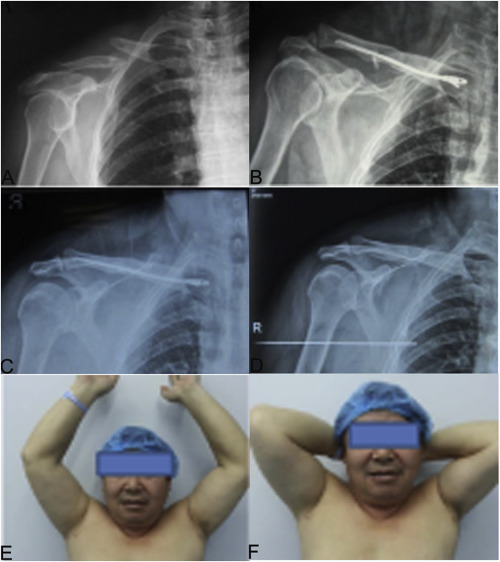

Fig. 3

Fig. 3.

A 46 years old man with right-sided displaced midshaft clavicular fracture underwent intramedullary nailing using our self-designed TEN. (A) the preoperative radiograph shows a midclavicular fracture (Robinson type IIB1 ); (B) the postoperative radiograph of the implanted TEN shows good position; (C) a radiograph obtained at 4 months postoperatively shows bone healing; (D) a radiograph obtained at 10 months after surgery shows the restoration of the normal clavicular shape after TEN removal; (E) the maximum abduction motion range of shoulder joint after operation; (F) the maximum flexion motion range of shoulder joint after operation.